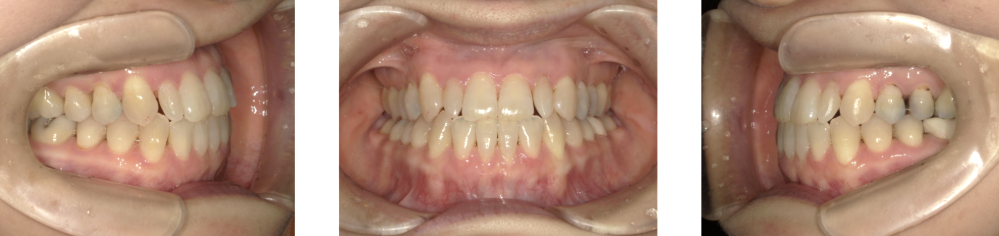

中等度受け口症例画像

中等度(前歯全体が反対咬合になっている)の方の場合

中等度の受け口は、上下の前歯全体が反対に噛んでいる状態で、かみ合わせのズレがはっきりとわかるタイプです。 前歯だけでなく、奥歯のかみ合わせにも影響が出ており、顎への負担や見た目のお悩みが強くなることが多いです。

治療方法としては、ワイヤー矯正(表側・裏側)やマウスピース型矯正装置を使い、前歯と奥歯の位置関係をしっかり整えます。歯並びのスペースが不足している場合は、歯列の幅を広げる調整や、必要に応じて抜歯を検討することもあります。

治療期間は約1年〜1年半で、計画的に歯を移動させることで、噛みやすさと見た目の改善が期待できます。